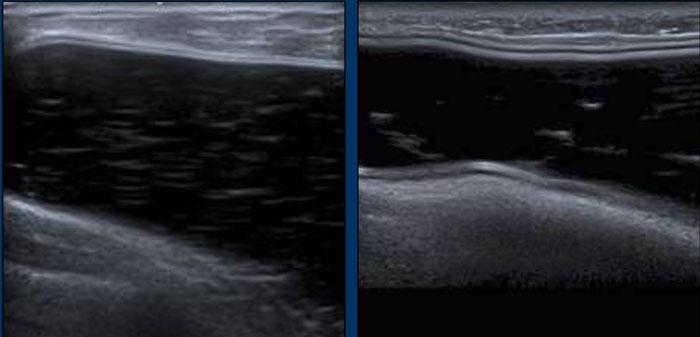

Nếp gấp hướng tâm (Radial folds)

Các đường thẳng hoặc đường cong sâu bên trong túi độn có thể khó đánh giá.

Liệu chúng là các nếp gấp hướng tâm bên trong hay là một phần của vỏ bọc bị xẹp do vỡ túi trong bao xơ? Cần tìm kiếm thêm các dấu hiệu khác và theo dõi đường đi của chúng để xem có liên tục với vỏ bọc hay không.

Trong một số trường hợp, cần chụp MRI để giải quyết vấn đề này.

Dấu hiệu thang (Stepladder sign)

Siêu âm có thể phát hiện vỡ túi trong bao xơ bằng cách xác định một chuỗi các đường thẳng hoặc đường cong tăng âm nằm ngang, tương đối song song với nhau, đi ngang qua bên trong lòng túi độn, thường được gọi là “dấu hiệu thang” (stepladder sign).

Điều quan trọng là không được nhầm lẫn dấu hiệu thang với các nếp gấp hướng tâm nổi bật bình thường.

Hình ảnh

Thêm các ví dụ về “dấu hiệu thang”.

Ở bệnh nhân này, vôi hóa bao xơ nặng nề đã che khuất tình trạng của túi độn.

Tuy nhiên, khi quan sát từ một góc độ khác, dấu hiệu thang cho thấy rõ ràng có vỡ túi.

Do vôi hóa lan rộng, không thể xác định chắc chắn liệu đây chỉ là vỡ túi trong bao xơ hay còn kèm theo rò rỉ Silicone ngoài bao xơ.